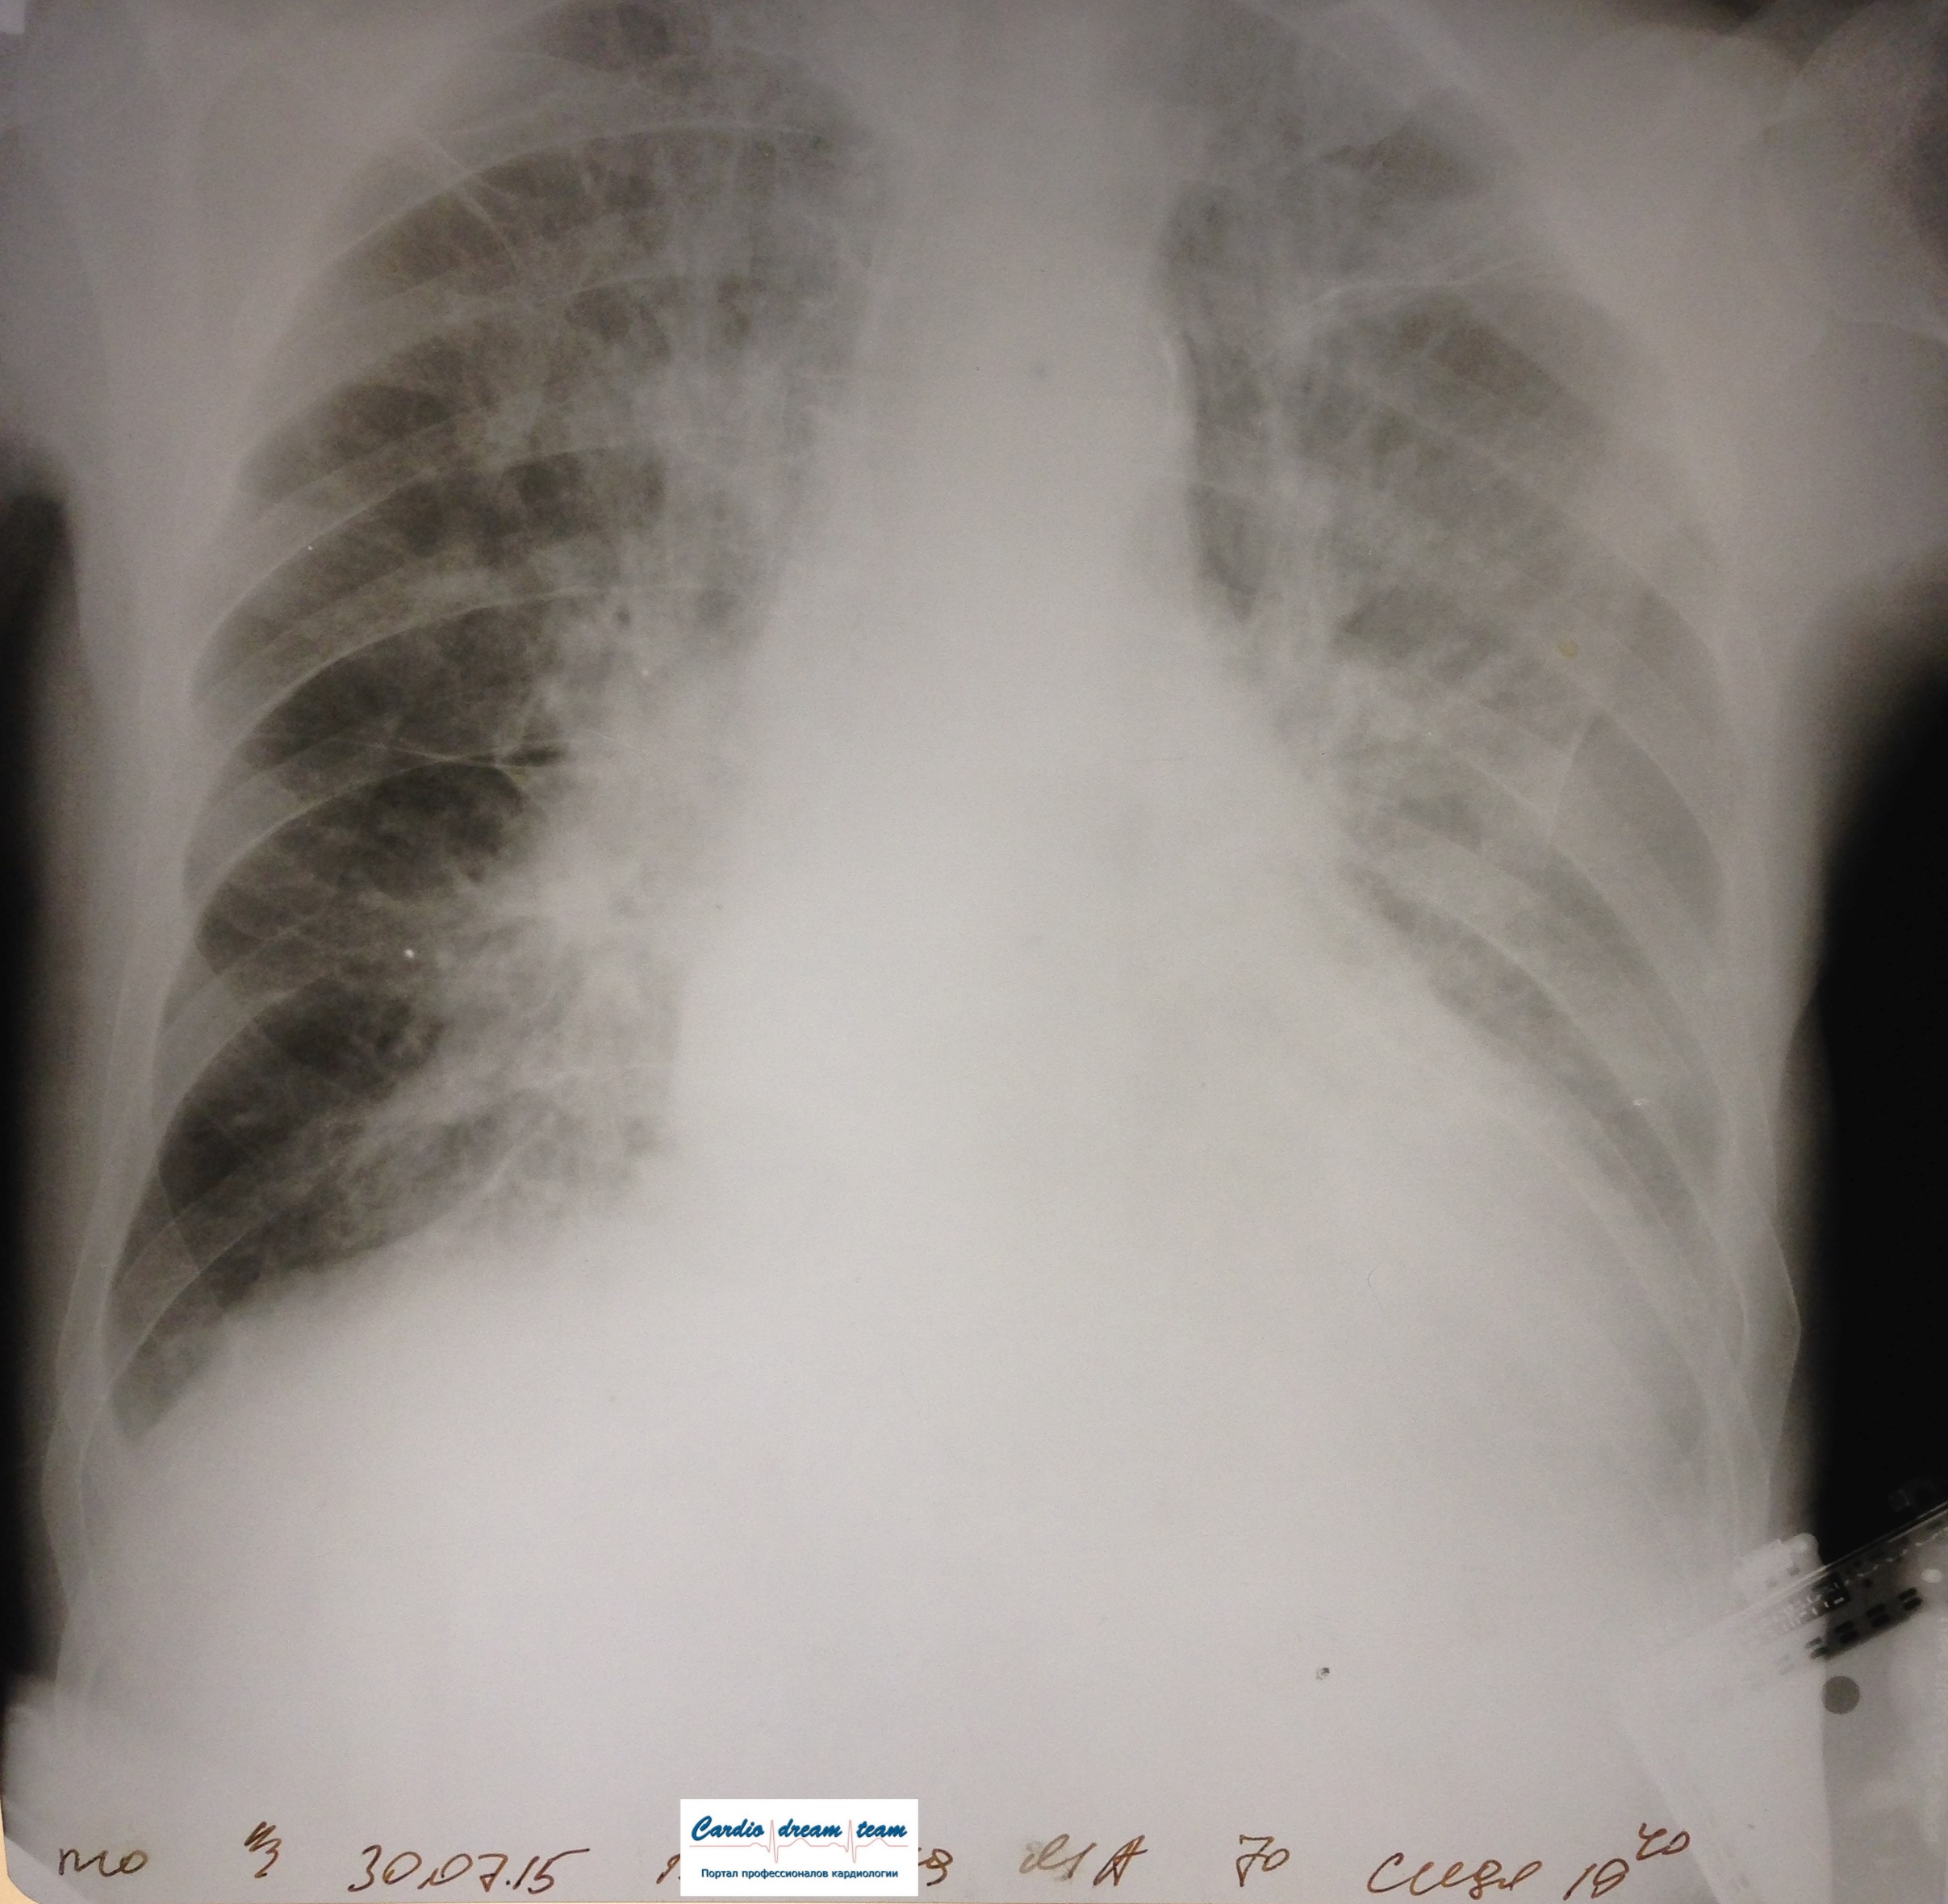

Не обсуждалась Дата 23-ИЮЛ-15 ОПИСАНИЕ: Проведена рентгенография органов грудной клетки в прямой проекции, положение лежа, условия ПИТ Легочные поля: неравномерно прозрачны за счет сосудистого обогащения, в базальных отделах с обеих сторон, отмечается сгущение легочного рисунка, за счет гиповентиляции, в плевральных полостях жидкость Легочный рисунок: Изменен по смешанному типу: обогащен за счет сосудистого компонента, деформирован за счет склероза. Корни: бесструктурны, расширены за счет сосудистого компонента, обогащены Синусы: определяется наличие жидкости по линии 5 ребра Сердце: широко лежит на диафрагме отмечается расширение границ сердечной тени влево, вправо экг-электроды. ЗАКЛЮЧЕНИЕ: Рентген-признаки 2-х стороннего гидроторакса с гиповентиляцией базальных сегментов.. Признаки застоя по МКК 2 степени (умеренно выраженный). Пневмосклероз. Р-признаки гипертрофии левого желудочка сердца. Склероз аорты.